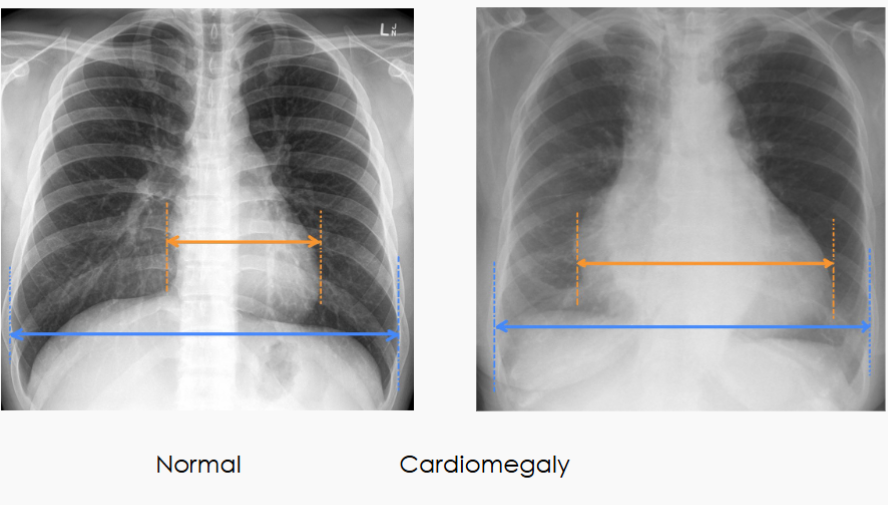

What is a common way to find cardiomegaly on X-ray?

The cardiothoracic ratio (CTR) aids in the detection

of enlargement of the cardiac silhouette (most often cardiomegaly but ALSO pericardial effusion)